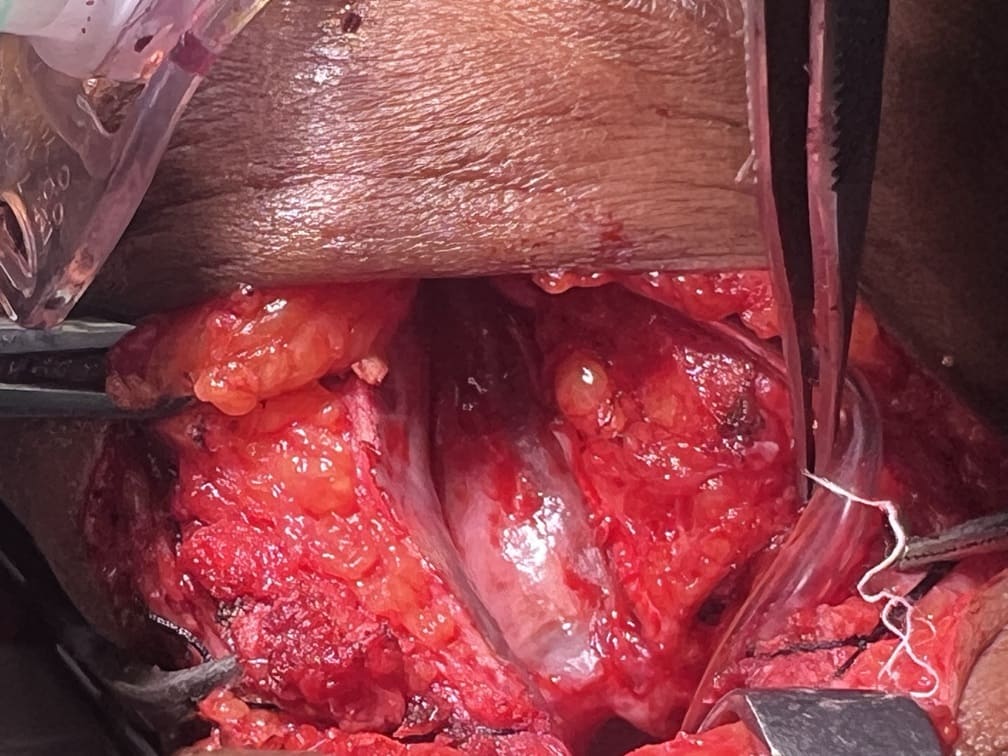

57 years old female suffering from left buccal mucosa growth involving left RNT and gingival surface of lip extending up to right angle mouth.left modified neck dissection with left distal segmental mandibulectomy with wide excision of left buccal mucosa with left RMT growth with excision gingival margin of lower lip with left pectoralis with right nasolabial flape done.

29-12-2025